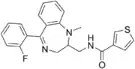

The pharmacodynamic response to an opioid depends upon the receptor to which it binds, its affinity for that receptor, and whether the opioid is an agonist or an antagonist. For example, the supraspinal analgesic properties of the opioid agonist morphine are mediated by activation of the μ1 receptor; respiratory depression and physical dependence by the μ2 receptor; and sedation and spinal analgesia by the κ receptor. Each group of opioid receptors elicits a distinct set of neurological responses, with the receptor subtypes (such as μ1 and μ2 for example) providing even more [measurably] specific responses. Unique to each opioid is its distinct binding affinity to the various classes of opioid receptors (e.g. the μ, κ, and δ opioid receptors are activated at different magnitudes according to the specific receptor binding affinities of the opioid). For example, the opiate alkaloid morphine exhibits high-affinity binding to the μ-opioid receptor, while ketazocine exhibits high affinity to ĸ receptors. It is this combinatorial mechanism that allows for such a wide class of opioids and molecular designs to exist, each with its own unique effect profile. Their individual molecular structure is also responsible for their different duration of action, whereby metabolic breakdown (such as N-dealkylation) is responsible for opioid metabolism.

Benzimidazoles

Benzimidazoles opioids are also known as nitazenes.